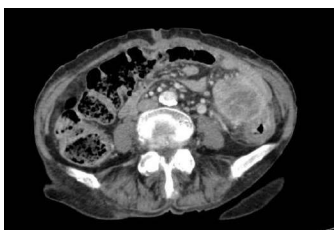

Uma paciente de 81 anos de idade, portadora de demência senil, hipertensão arterial, diabetes tipo 2 e artrite reumatoide, sem antecedentes familiares de neoplasia, deu entrada no pronto-socorro com dor abdominal em hipogastro e fossa ilíaca esquerda, sem irradiação há duas semanas, com piora progressiva. Estava em investigação por constipação intestinal com médico da unidade de saúde próxima à sua casa. Durante a investigação, realizou uma tomografia computadorizada de abdome total com contraste, que evidenciou a imagem abaixo.

Com base nesse caso hipotético, assinale a alternativa correta.